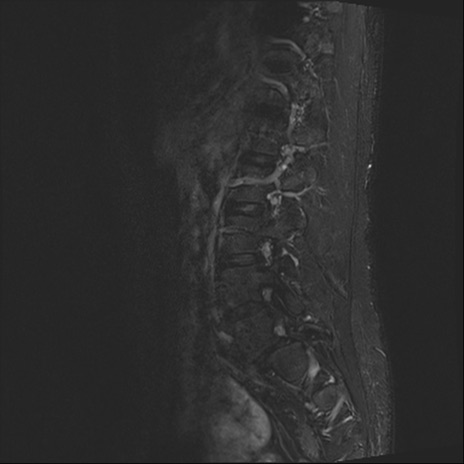

腰椎MRI

T2WI(横断像)